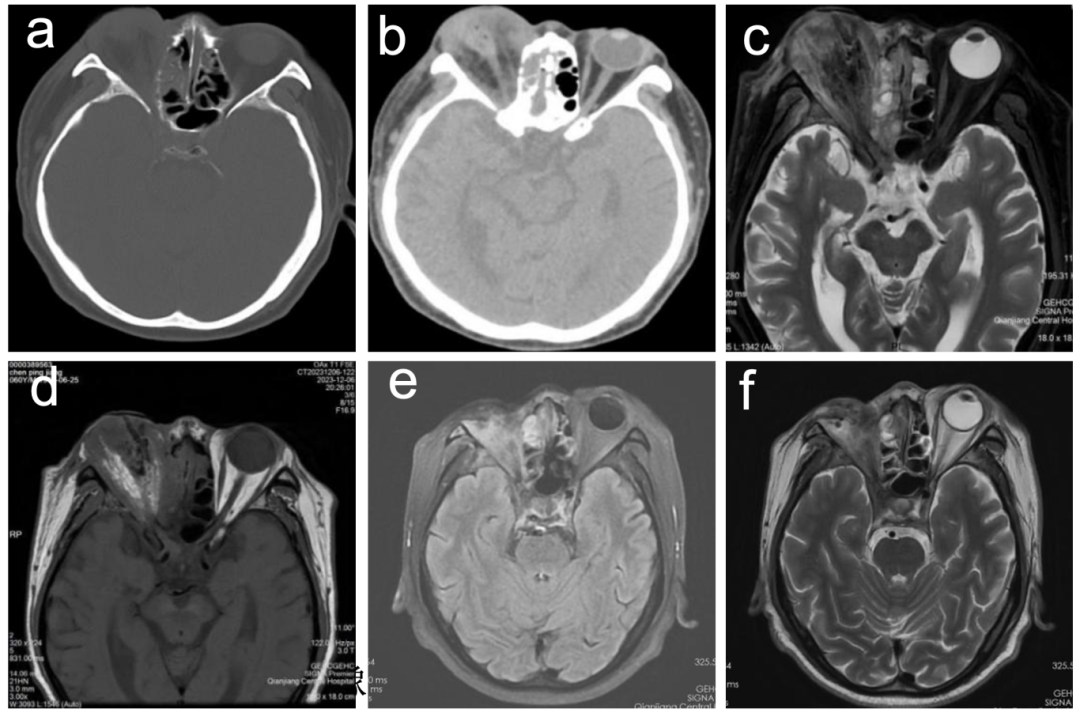

行CT检查(图3a与3b),显示右眼球及附属结构异常改变,颅脑未见确切异常征象。

入院第10天,右眼睑及结膜水肿逐渐缓解,眼部恶臭分泌物明显减少,考虑米根霉血管神经侵袭性极强,行MRI检查(图3c与3d),提示仍有坏死组织残留。遂行右眼眶探查+眶内容物摘除+眶隔修补+筋膜组织瓣成形+结膜囊成形+负压引流,术中出血约15mL,术后结膜囊涂妥布霉素地塞米松眼膏。术中组织标本病理切片经苏木精和伊红染色(HE染色)提示:急性化脓性炎伴肉芽肿形成,并查见宽大无隔真菌菌丝(图2e与2f),革兰染色还查见革兰氏阳性球菌,培养仅检出粪肠球菌。

出院后使用那他霉素滴眼液联合口服艾沙康唑胶囊完成40天治疗。随访40天行MRI检查(图3e与3f),眼部感染病灶明显吸收,颅脑未见异常。空腹血糖6.34mmol/L,糖化血红蛋白6%。整个治疗周期该患者的临床治疗见表2。

图3影学像结果

a、b:第一次术前CT结果眼眶内侧壁部分骨质吸收,眼球及附属结构损伤;c、d:第二次术前MRI结果眼球、球后脂肪、内外直肌 、视神经毁损;e、f:随访40天MRI结果眼部感染病灶明显吸收,颅脑未见异常